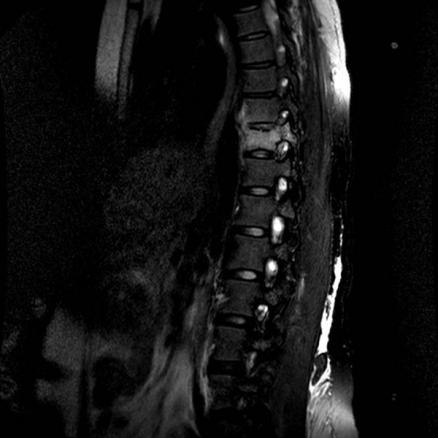

La Revue du Praticien - Hélène Leroy IRM. Hypersignal du corps vertébral de T10 avec fuseau prévertébral : mal de Pott (séquence T2).